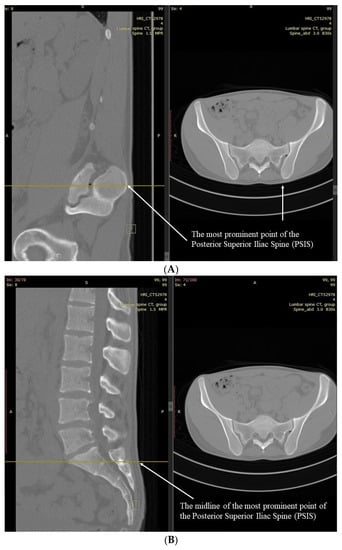

2. Methods